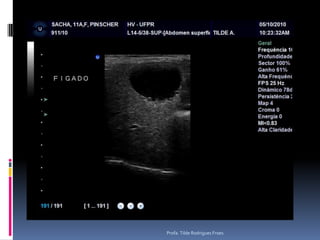

Animal: Sacha, canino, fêmea, 11 anosAvaliação – suspeita de HiperadrenocorticismoProfa. Tilde Rodrigues Froes

Animal: Sacha, canino,fêmea, 11 anosAvaliação – suspeita de HiperadrenocorticismoProfa. Tilde Rodrigues Froes